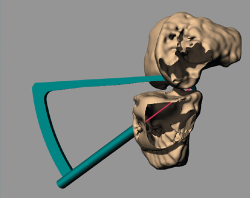

Figure 1. Design of the guide on the virtual reconstruction of the knee.

Manufacture of the guides was based on virtual reconstruction of the joint using the MITK (Medical Imaging Interaction Toolkit) free access software for the development of medical image processing applications, developed by the Medical and Biological Informatics (MBI) Division of the German Cancer Research Center. As image source, we used the DICOM (Digital Imaging and Communication On Medicine) files corresponding to 1-mm transverse, sagittal and coronal sections of the scan of each patient, obtained with a high-field (1.5 T) Siemens MRI system.

Using Rhinoceros®, Rhino 6 (TLM, Inc.), each guide was designed on a generic basis, followed by adaptation to the virtual reconstruction of the knee of each patient, with an entry point in the anteromedial cortical layer of the tibia located medial to the anterior tibial tuberosity (ATT), adapted to the bone relief, and two exit points in the insertion zone of the posterior horn of the internal meniscus (Figure 1). Each guide housed two 3-mm bores for the creation of two parallel tunnels (Figure 2). The tunnel angle was 60° in all cases, with variation in each case of the morphology of the intraarticular portion of the guide in order to fully adapt it to the anatomy and avoid impacting against the tibial spines or medial femoral condyle.